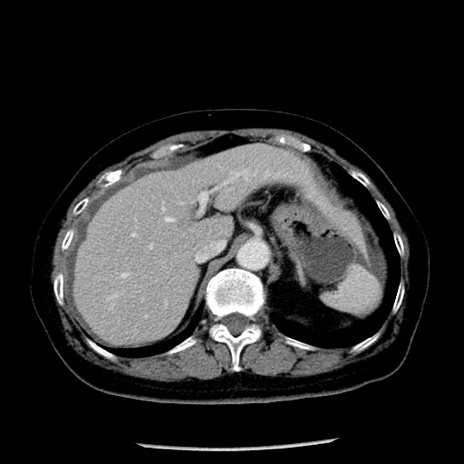

症例13(横断像)

【症例】70歳代女性

【主訴】腹痛、嘔吐

【現病歴】15時間程前(昨晩)より腹痛あり。今朝になっても症状の改善なく、嘔吐あり。腹痛も増悪あり、救急外来受診。

【既往歴】子宮癌全摘術後

【身体所見】意識清明、BP 121/72mmHg、P 74bpm、SpO2 100%(RA)、腹部:平坦・軟、腸雑音ほぼ聴取せず。下腹部・心窩部・臍左上に圧痛あり。反跳痛なし。

【データ】WBC 10600、CRP 0.15